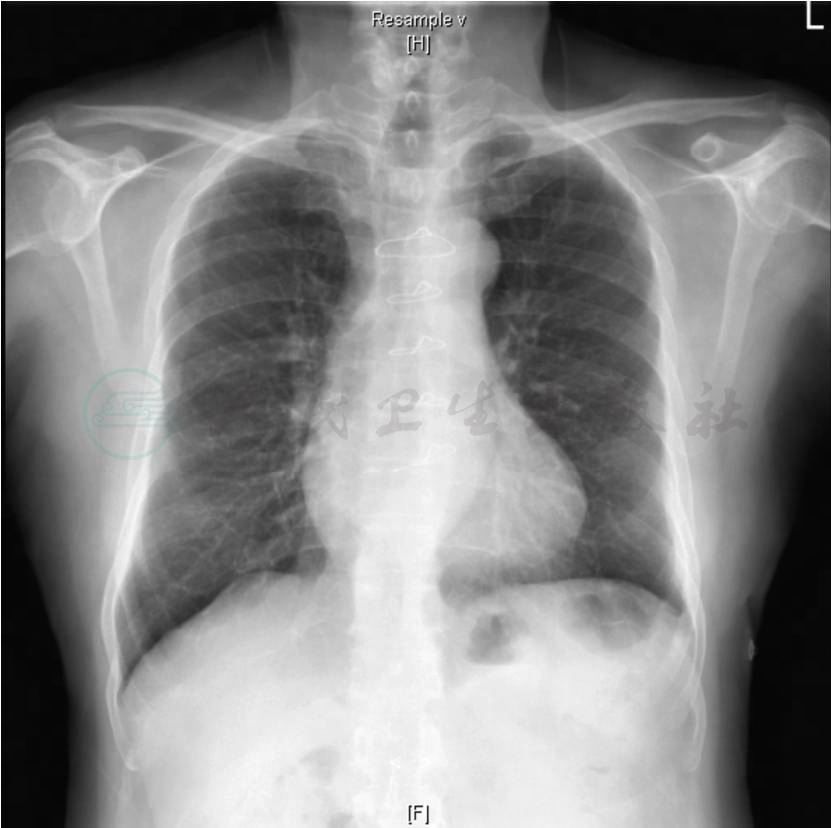

最近一次胸部X线检查(图17)显示:两肺纹理大致正常,未见实变;主动脉结偏宽,边缘少许钙化;肺动脉段平直;左室圆隆;心胸比0.52。

图17 2013-9-10心脏远达片